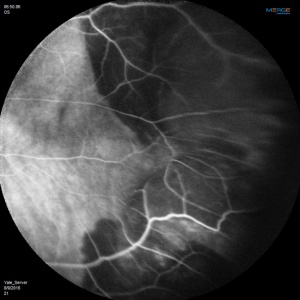

Fluorescein Angiographic Findings

Blockage of choroidal fluorescence related to hemorrhage (sub-retinal, sub-RPE) and window defect from peripheral atrophic RPE changes are the most common FA findings. Other findings include diffuse peripheral hyper- or hypofluorescence that correlate to RPE atrophy or hyperplasia. Choroidal neovascularization is seen on rare occasions (in 2 out of 173 eyes in the case series by Shields[5] and in series by Bec et al[23]), but even in eyes without choroidal neovascularization, ICG angiography may reveal abnormal choroidal neovascular network. Instances of abnormal retinal circulation--peripheral patches of nonperfusion, ischemic hemi-central vein occlusion, and delayed retinal filling--were seen in a few patients in Mantel's 2012 case series[13] but without clear significance or relevance.

ICG Angiographic Findings

In Mantel's 2009 series of 56 eyes with PEHCR[7], 20 eyes underwent ICG-A, and among them, 6 (30%) had pathologic choroidal vascular networks that "resembled those observed in polypoidal choroidal vasculopathy" (none of them had associated FA findings of neovascularization). Late hyperfluorescence was seen in 12 eyes, and in two eyes hypofluorescence resulting from hemorrhage-related blockage was seen. In Mantel's 2012 case series of 48 eyes in 40 patients[13], the proportion of eyes with pathologic choroidal vascular network was 50% (24 eyes, again none of the eyes had CNV seen on FA), albeit the ICG-A system in use was different in 2012 series compared to 2009 case series. Additionally, peripheral poly-like choroidal telangiectases were seen in nearly 70% of the eyes along with dilated choroidal veins.

Mantel claims that his angiographic findings objectively establish commonalities between PEHCR and PCV and stops short of asserting that PEHCR is a peripheral manifestation of or caused by PCV. Note that the neovascular origin of PEHCR is a hypothesis and not yet backed up by histologic evidence.